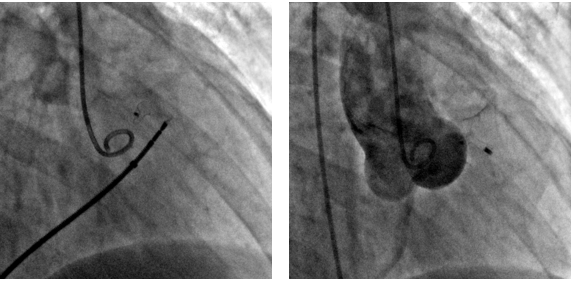

Чрез-артериальным доступом через дефект проведен проводник 0,035, кончик проводника направлен в ствол ЛА, выполнен захват проводника ловушкой типа «лаcсо», проводник выведен через венозный доступ, таким образом сформирована артериовенозная петля. Методика закрытия данного дефекта не отличалась от закрытия стандартного ДМЖП, однако учитывая непосредственную близость устья ПКА, принято решение имплантации PDA окклюдера, так как диск окклюдера несколько меньше и тоньше чем у VSD окклюдеров. Венозным доступом по проводнику проведено доставочное устройство SFP 6 Fr, по которому доставлен PDA окклюдер «LifeTech»XJFD0608. Дистальный конец окклюдера расположен в правом коронарном синусе, а тело окклюдера закрывает полость дефекта. На контрольной ангиографии сброса контраста через тело окклюдера не выявлено. Правая коронарная артерия не скомпрометирована. Давление в ПЖ 33/2 торр. Осложнений во время процедуры не было. Время операции 17 мин, рентгеноскопии 9 мин.( Рис. 4,5)

Рисунок 5. Окончательный вид операции.